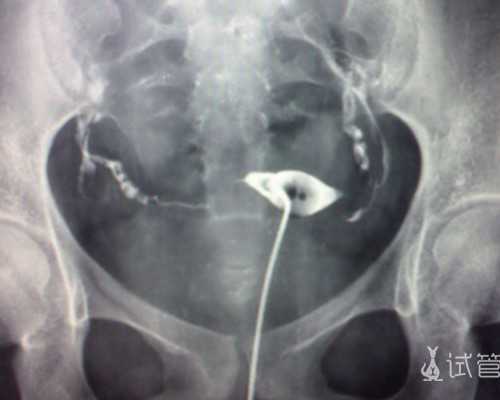

通过高速离心处理将采集到的孕妇静脉血标本进行分层,将样本中含有大量DNA物质的上层清液置入全新的无菌试管中保存。这时候专业医师就用相关的试剂将其中的DNA物质提取出来,染色后在紫外线灯光下观察。

若宝宝为男,那就会看到SRY的条带,没有SRY条带就说明宝宝为女,为什么会通过这样的方式确定男女呢?因为研究表明,在男性的基因中,区别于女性,他们的Y染色体上有特有的SRY基因,如果在这些DNA片段中发现了SRY条带的话,那就是宝宝为男性。